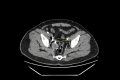

The Endovascular Embolization of an Isolated Internal Iliac Artery Aneurysm: A Case Report

While isolated internal iliac artery aneurysms (IIIAAs) are rare entities, they are associated with a high mortality rate if ruptured. IIAAs are usually asymptomatic and can be discovered accidentally during imaging for any other causes. The treatment options vary according to the signs, symptoms, size of the aneurysm, and the patient's general condition. While surgery used to be the first option of treatment earlier, with the advances in the field of endovascular intervention, endovascular repair of IIIAA has emerged as the first option of treatment if applicable.